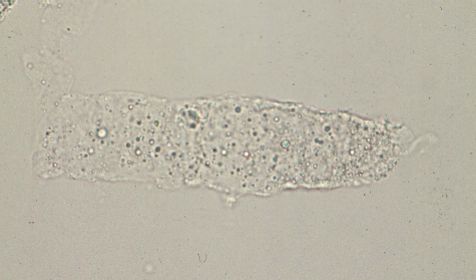

脂肪円柱

円柱基質内に3個以上の脂肪球が含有したものを脂肪円柱と呼ぶ